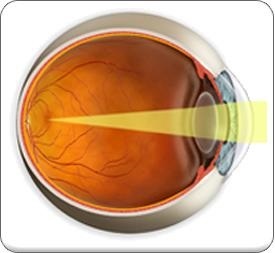

Lens a ochiului - această structură anatomică a segmentului anterior al ochiului, în mod normal, ar trebui să fie foarte clar. Principiul de funcționare a cristalinului - focalizări reflecta razele de lumină de obiect în zona maculară. Imaginea de pe retina ochiului a fost clar, ar trebui să fie transparente. Atunci când lumina cade pe retina, un impuls electric, care intră prin nervul optic spre centrul vizual al creierului. Sarcina a creierului - de a interpreta ceea ce văd ochii.

Rolul lentilei în funcționarea sistemului unei persoane este foarte importantă. În primul rând are o funcție de ghidare a luminii, adică, permite trecerea fluxului de lumină la nivelul retinei. Funcțiile obiectiv cu transmisie a luminii sunt furnizate de transparența sa.

În plus, agenția a fost implicat activ în ruperea luminii și are o putere de aproximativ 19 dioptrii. Datorită lentilei furnizate de funcționarea mecanismului acomodativă prin care ajustează în mod spontan focalizarea imaginii vizibile.

Acest organism ne ajută privit cu ușurință de la obiectele îndepărtate pentru cei care sunt aproape de cele furnizate prin schimbarea puterii de refracție a globului ocular. Odată cu reducerea fibrelor musculare, care înconjoară lentila, există o scădere a tensiunii capsulei și modificarea formei lentilei optice a ochiului. Devine mai convex, astfel în mod clar vizibil plasate în apropierea obiectelor. Atunci când mușchiul se relaxează, obiectivul devine plat, vă permite să vedeți obiectele situate departe.